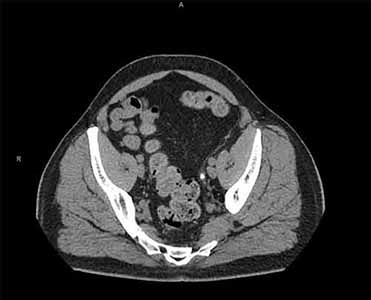

Left-sided Abdominal Pain in a 45-yr-old Man

Test Result 2

CT scans without contrast of the abdomen and pelvis are obtained and are shown.

Select each image to review.